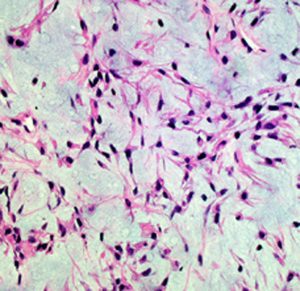

毛様類粘液性星細胞腫の病理像です。関質が広くて粘液用の物質が貯留されています。これは手術で取る時にドロドロの腫瘍に見えますから,ちょっと硬い普通の毛様細胞性星細胞腫とは判別できます。この病理像をもつ腫瘍は,患者さんの年齢が年長児になっていくと,自然に変化して普通の毛様細胞性星細胞腫に変わっていきます。腫瘍も年をとるのだと考えられます。ですから,毛様類粘液性星細胞腫は特殊なものではなくて,毛様細胞性星細胞腫の赤ちゃんです。右側の画像では,血管中心性に腫瘍細胞が配列するangiocentric patternがみられます。